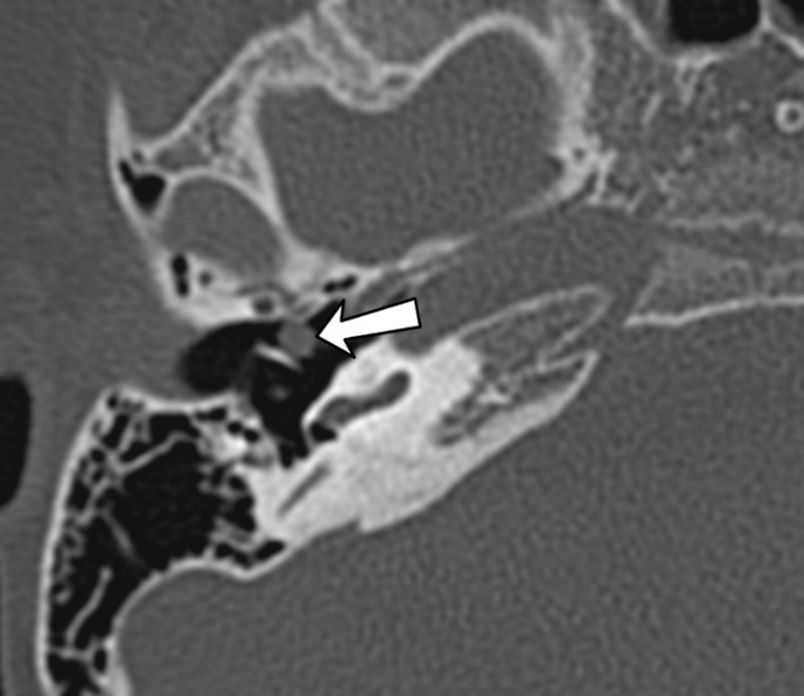

КТ височных костей. Холестеатома отмечена стрелкой